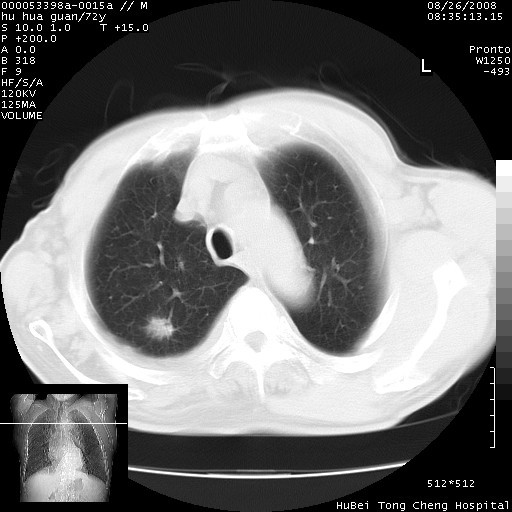

标题: CT15582:M,72Y。请老师帮分析胸部病变。 [打印本页]

标题: CT15582:M,72Y。请老师帮分析胸部病变。

可以明确的说。肯定不是主动脉夹层破裂出血!考虑为淋巴瘤或间叶组织来源的恶性肿瘤可能性大。右肺小结节建议薄层观察,如能发现恶性征象,那椎前改变就考虑为转移所致。至于双侧少量胸水乃静脉血回流受阻所致。

图像及窗宽窗位均不理想。周围性肺癌/胸腔积液/纵隔积液。

1、右肺周围性肺癌、胸腔积液(双)

1、右上肺结节病变,肺泡癌不除外,请随诊;左下肺近后纵隔病变,考虑纵隔型肺癌侵犯大血管可能;

2、右下肺背段少许炎症,双侧胸腔积液,右下肺纤维索条。

降主动脉前移位,后纵隔占位

后纵隔占位,降主动脉前移位;双侧胸腔积液;应排外食管病变侵犯血管可能;